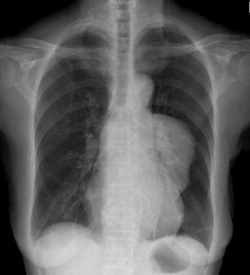

病历摘要:胸腺瘤患者,女性,55岁,重症肌无力多年,发现贫血1年余。查体.双侧眼睑下垂,面色苍白。行胸部平片检查。